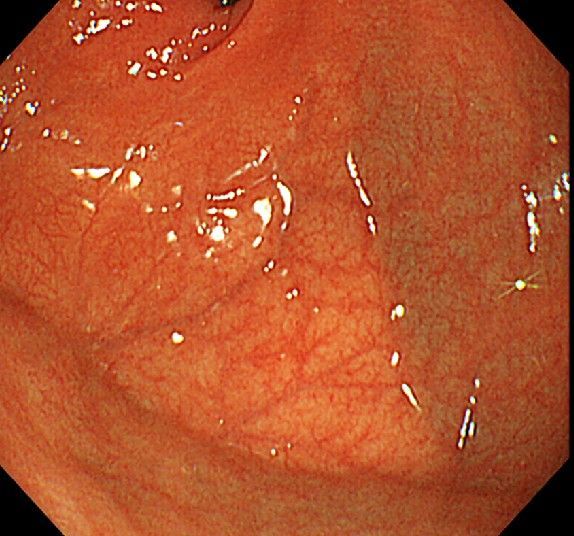

위 내시경을 찍었는데 위염 종류 사진을 알 수 있을까요? (사진 많습니다..)

한달 전 쯤에 소화불량과 속쓰림이 3개월 동안 약을 먹어도 낫지 않아 위 내시경을 찍었는데 위에 염증이 많이 있다는 이야기를 들었습니다...그런데 상태가 얼마나 안 좋은지 어떤 종류의 위염인지에 대해서는 물어봐도 안 알려주셔서 여기에라도 올려서 여쭈어봅니다... 제 상태가 얼마나 심각한 걸까요..

사진상으로 보아서는 정상에 가까운 점막상태이거나 약간의 표재성 위염이 있는 정도로 보입니다.

홍반성 위염이 있으며 경증의 역류성 식도염이 있습니다

위내시경상으로는 특이소견이 없다고 보셔도 됩니다